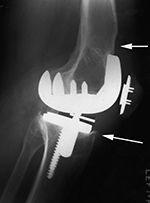

A noncemented total knee arthroplasty is present with a metal backed patellar component. There is also a polyethylene locking clip which locks the tibial polyethylene into the tibial base plate. The anterior cortex of the femur is notched and eroded (top arrow). There is also subtle subsidence of the tibial component (bottom arrow). From Benjamin, 1994 |

| 69 year-old man with revision of an infected right knee prosthesis (two left panels). A rotating hinge knee implant was placed. Note the antibiotic beads about the medial aspect of the implant. The two fixation screws and wire are from prior surgery. There was implant failure with disruption of the implant six weeks later (two right panels). |